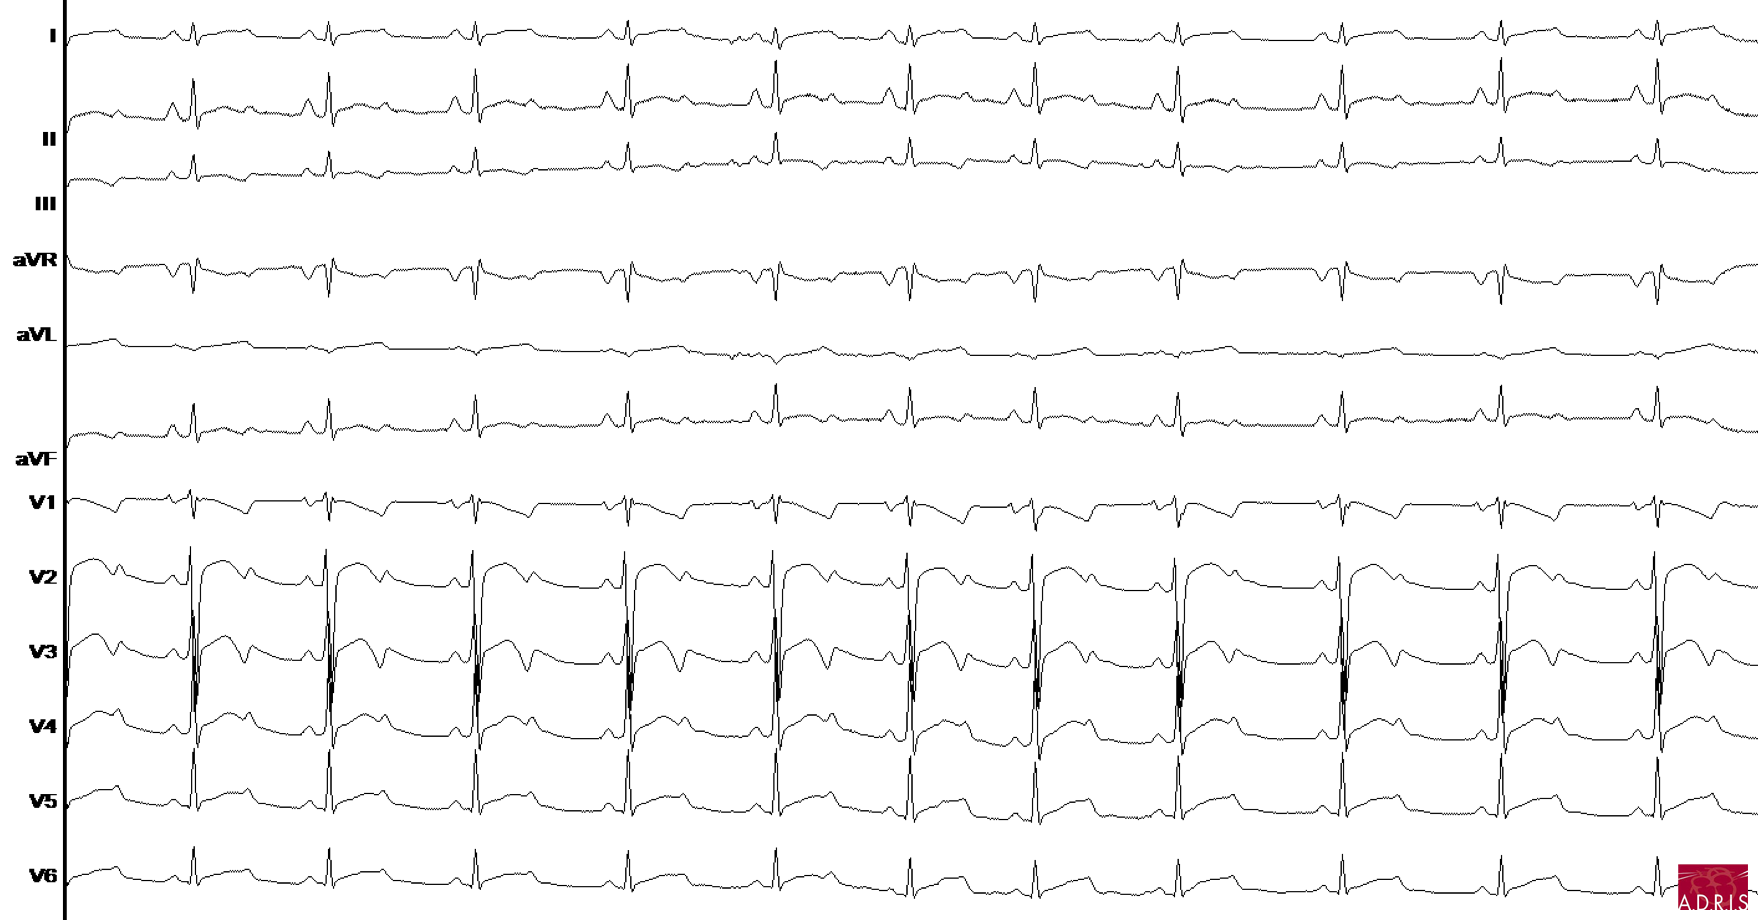

3 principales formes

LQT1 : 40 - 45 % des cas

- mutation dans le gène KCNQ1 impliqué dans le courant Iks

- onde T avec base large

LQT2 : 30 - 35 % des cas

- mutation dans le gène KCNH2 impliqué dans le courant Ikr

- onde T avec aspect de double bosses

LQT3 : 10 % des cas

- mutation de la gène SCN5A impliqué dans le courant INa

- segment JT long, onde T pointue